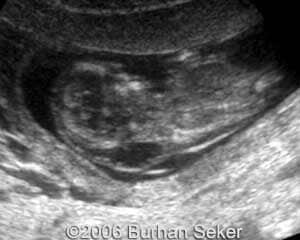

This a fetus with a cystic hygroma diagnosed at 13 weeks and 3 days. Karyotype was normal. The pregnancy was interrupted at 16 weeks.

At 13 weeks